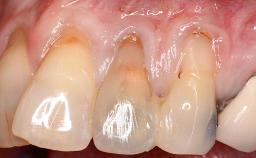

Implant Placement in the Esthetic Zone and Coverage of Multiple Gingival Recessions

This case illustrates use of a modified ‘tunnel’ technique, which has been shown to be highly effective in root coverage procedures. The tunnel technique is used to achieve soft-tissue augmentation across the anterior area, including the planned implant site, using collagen matrix as grafting material. The patient is a 47-year-old woman with high esthetic expectations. Her main concern was the appearance of the anterior teeth and their “elongation”.

Soft Tissue Anatomy Intact Defective

Soft Tissue Contour and Volume Significantly deficient